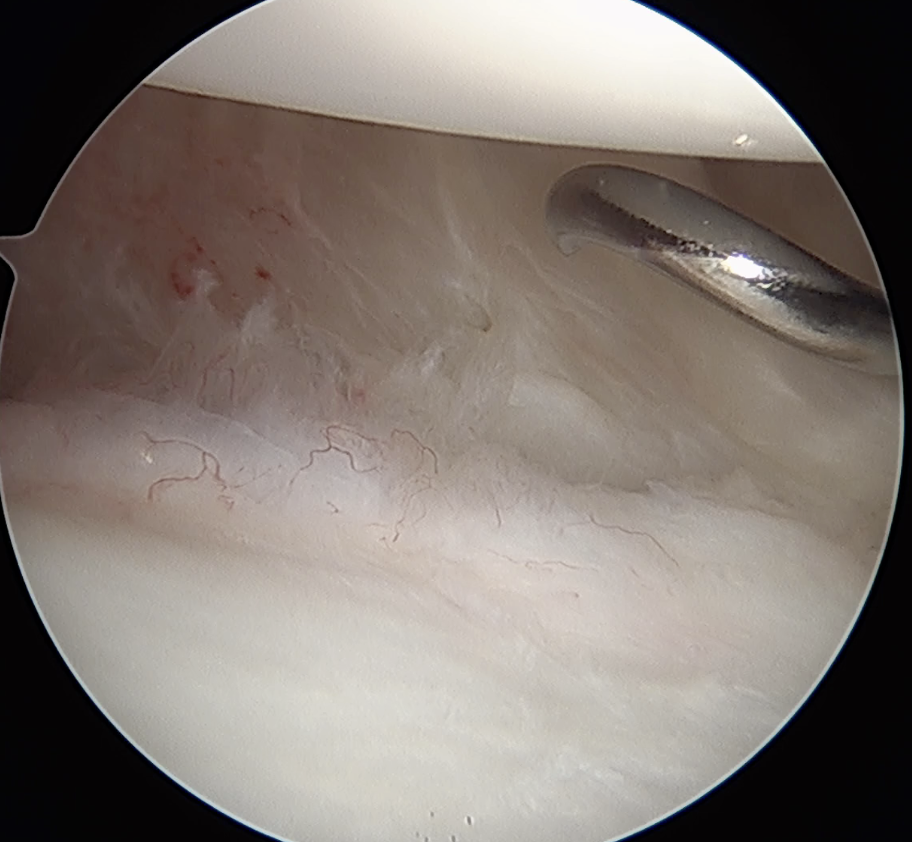

Posterior capsular plication

- option 1: Suture plicate capsule to labrum

- option 2: Anchors in glenoid and use to plicate capsule to labrum

Posterior capsular plication with suture anchors